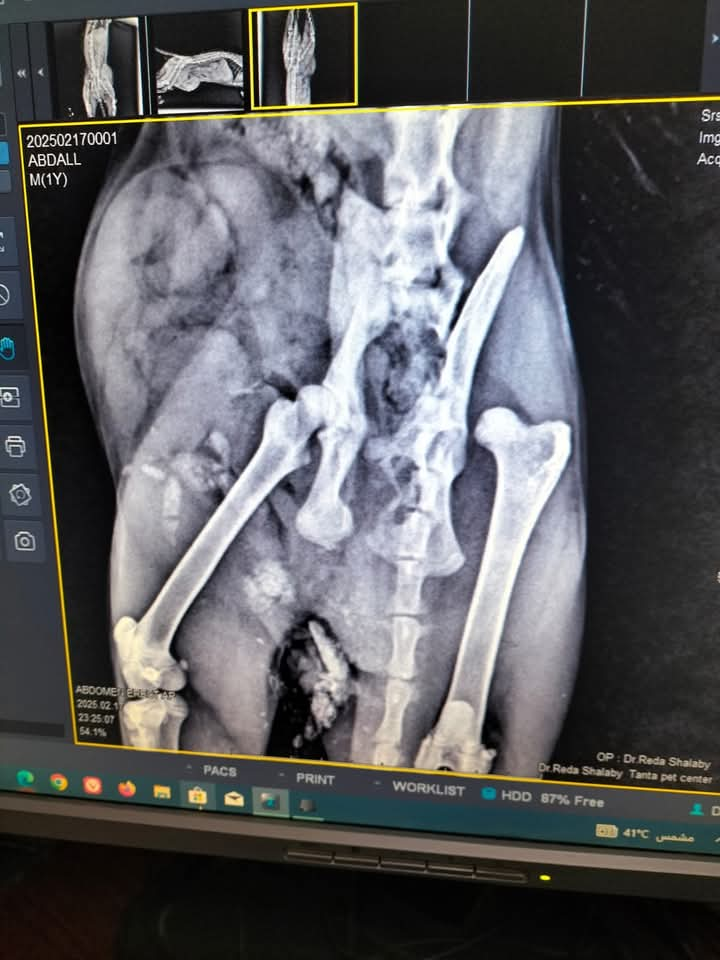

أجرى فريق أطباء عيادة طب وجراحة الحيوانات الأليفة، بديوان عام مديرية الطب البيطرى بالغربية، جراحة لإصلاح فتق اربى بجدار البطن باستخدام شبكة جراحية، لقط نتيجة لحادث سيارة أدى إلى احتجاز والتصاق الأمعاء الدقيقة والمثانة داخل غلاف الفتاق، والذى أدى ايضا لحدوث كسر بعظام الحوض، وخلع فى مفصل الحوض للرجل اليمنى على أن يتم التعامل الجراحى لكسر الحوض وخلع المفصل فى مرحلة لاحقه عقب استقرار الوضع الصحى للحالة واكتمال تعافيها من الجراحة الأولى Right Inguinal Hernia repair with polypropylene surgical mesh

الاشعة للقط

الاشعة